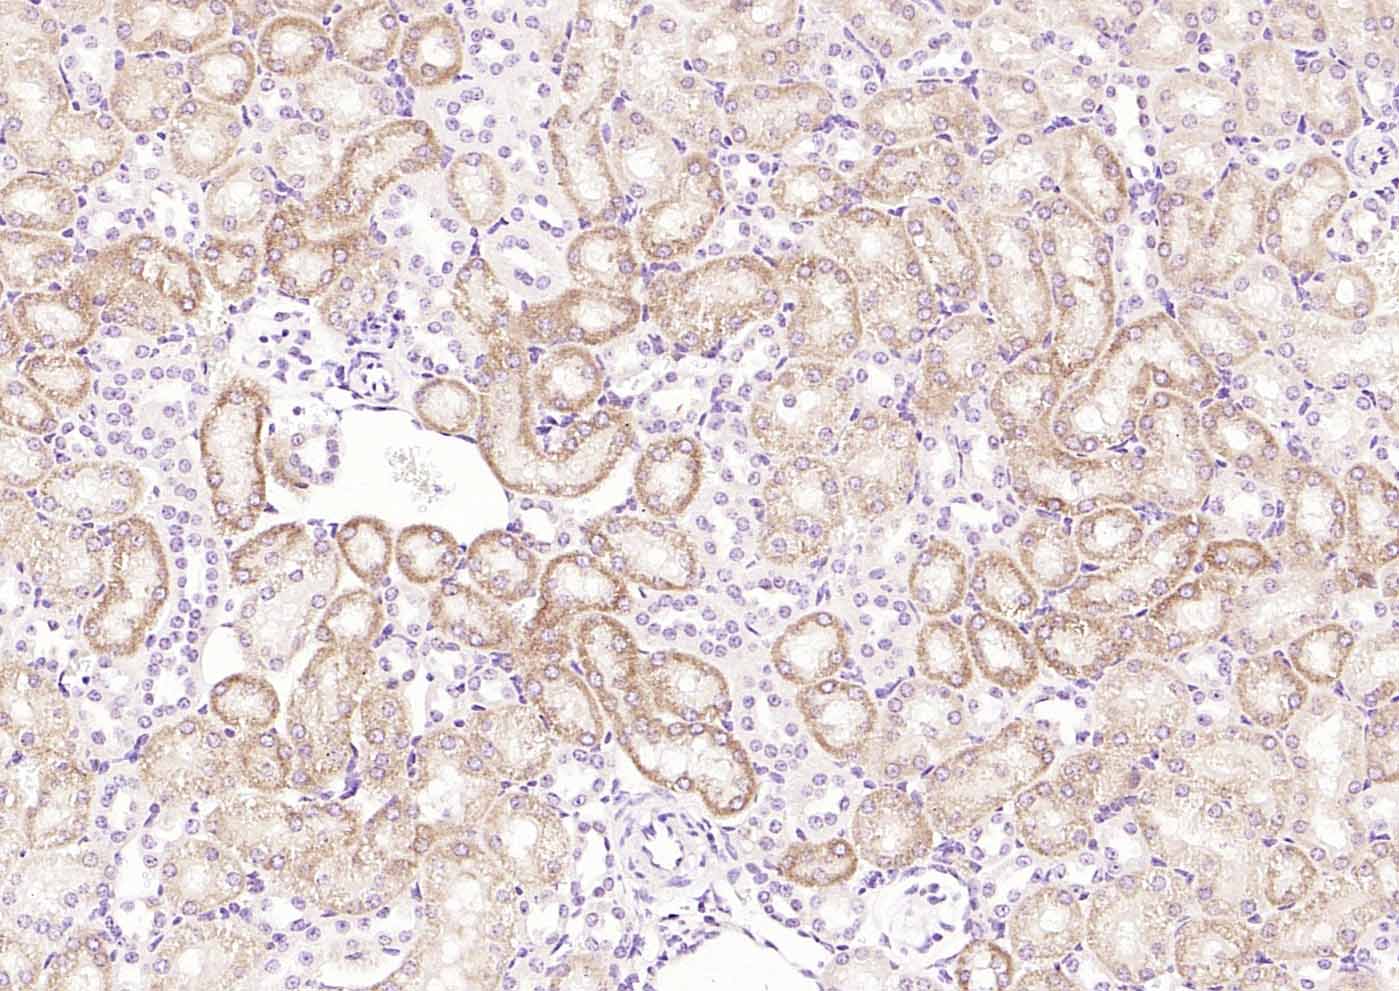

| {IHC-P} | {1:100-500} |

Primary: Anti- RelB (bs-3562R) at 1/1000 dilution

Secondary: IRDye800CW Goat Anti-Rabbit IgG at 1/20000 dilution

Predicted band size: 64 kD

Observed band size: 64 kD